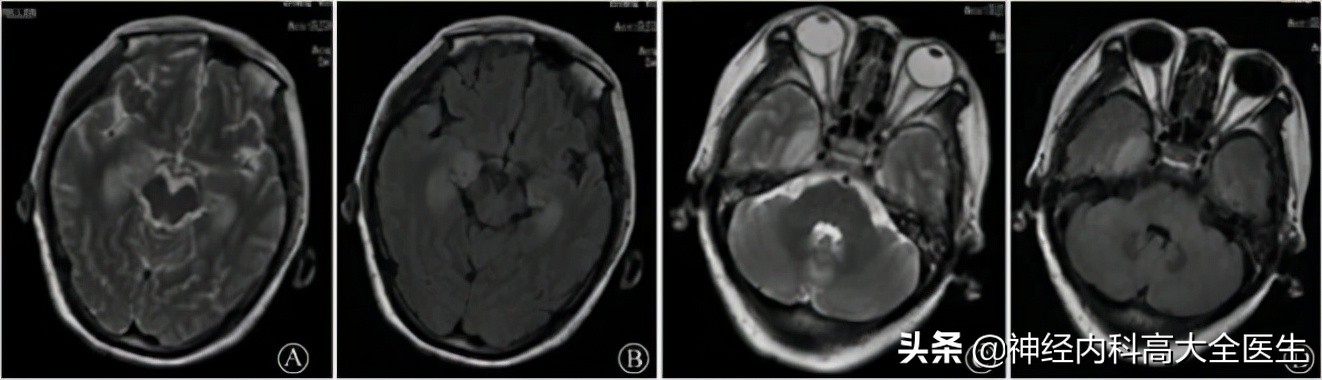

抗GABA-b受体脑炎影像学

抗GABAb受体脑炎急性期仅有 50%的患者头颅MRI异常,以颞叶和海马最易累及,多表现为T2/Flair高信号